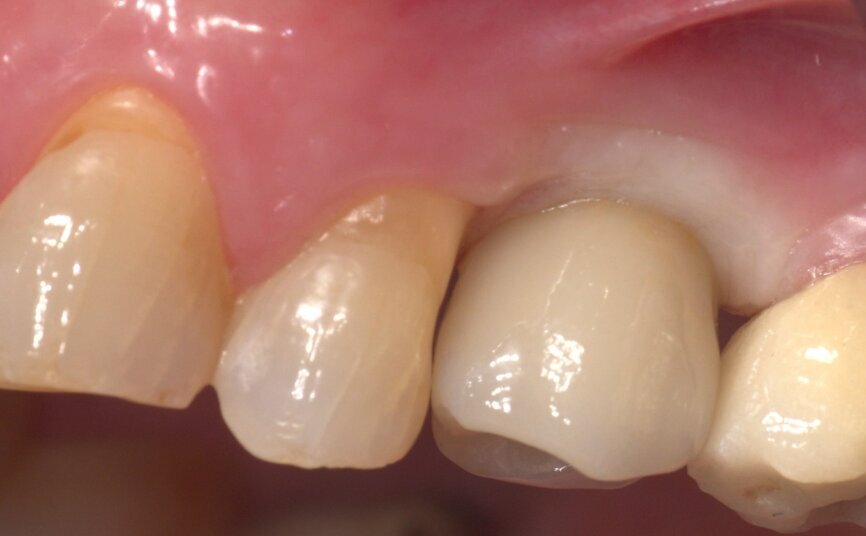

Returning to the patient, the healing caps were removed, and the crowns were placed. The occlusion was checked and contacts were inspected (Figs. 40–43). Screw holes were sealed with PTFE and a temporary filling material.

The patient and dentist were completely satisfied with the final result regarding aesthetics, health and function. The patient returned for a check-up one week later and was very satisfied with the aesthetic and functional outcomes of the treatment (Fig. 44).